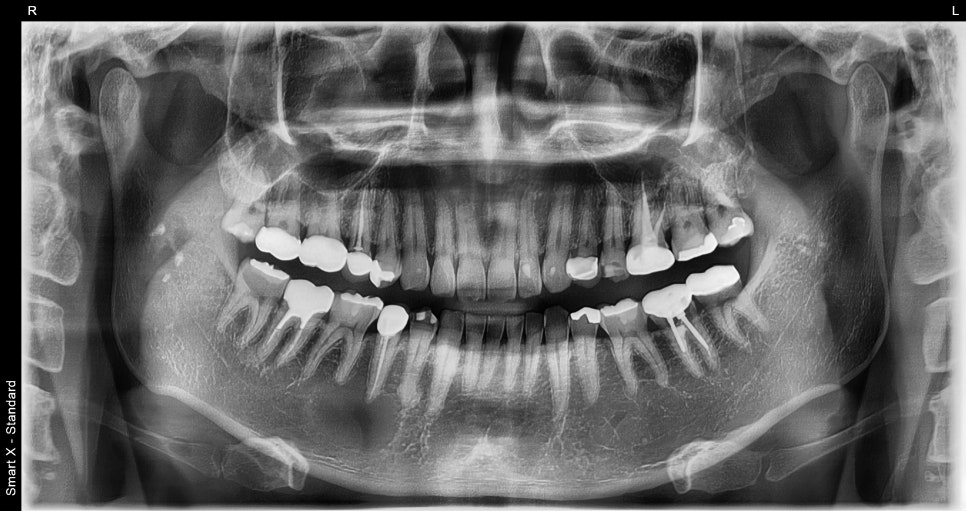

As a result of panoramic imaging and CBCT (3D CT) examination,

a well-defined radiolucent lesion was identified within the mandible in that area.

Diagnostic result: suspected benign tumor-like lesion within the mandible. The lesion was a circular cystic lesion about 2.5 cm in size, and unlike inflammation, it was a well-demarcated lesion distinguishable from the surrounding tissue.

Differential diagnosis: possibility of periapical cyst / cementoblastoma / odontogenic tumor, etc.

📸 Before surgery

– Cystic lesion at the periapical area